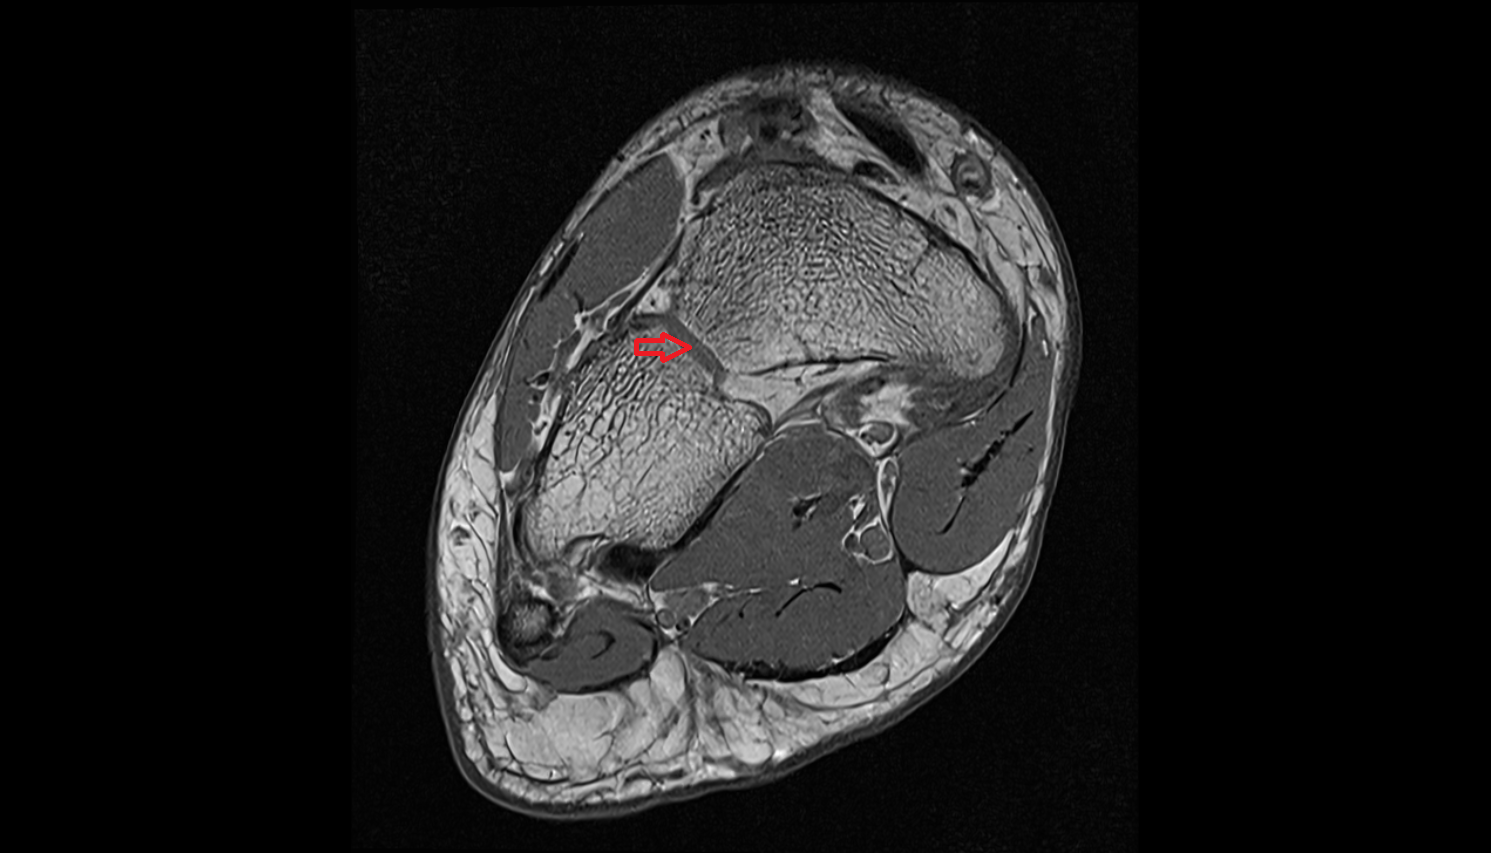

- Talus

- Body of talus

- Calcaneus

- Sustentaculum tali

- Medial malleolus

- Lateral malleolus

- Ankle joint

- Tibialis posterior muscle

- Flexor digitorum longus muscle

- Flexor hallucis longus muscle

- Quadratus plantae muscle

- Abductor hallucis muscle

- Abductor digiti minimi muscle

- Tibialis posterior tendon

- Flexor digitorum longus tendon

- Flexor hallucis longus tendon

- Achilles tendon

- Posterior tibial artery

- Anterior tibial artery

- Fibular artery